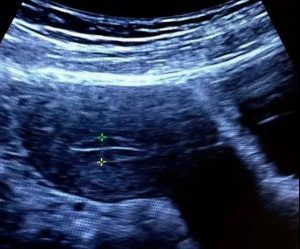

这时候很多比较纠结的亲会说,可我怎么知道自己的胚胎到底好不好,内膜条件到底好不好呢?一般来说自然排卵后1周,内膜可以达到9mm及以上的话,说明内膜比较肥沃。不过大大认为,每个人的基数不一样,内膜就如人的高矮一样,各有不同,内膜薄胚胎就一定无法着床的想法是不科学的。相对于内膜的薄厚,内膜的形态是更为重要的参考指标。排卵前如果可以清晰地看到三线征,就说明内膜形态还是很良好的,这样的内膜即便薄一些,也是非常有着床潜力的。